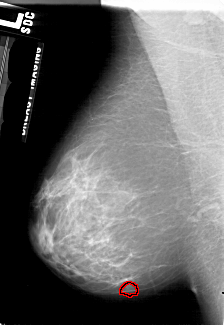

A_1758_1.RIGHT_CC

RIGHT_CC LINES 5476 PIXELS_PER_LINE 3571 BITS_PER_PIXEL 12 RESOLUTION 43.5 NON_OVERLAY

FILE: A_1758_1.LEFT_CC.OVERLAY

TOTAL_ABNORMALITIES 1

ABNORMALITY 1

LESION_TYPE MASS SHAPE LOBULATED MARGINS OBSCURED

ASSESSMENT 3

SUBTLETY 4

PATHOLOGY BENIGN

TOTAL_OUTLINES 1

BOUNDARY